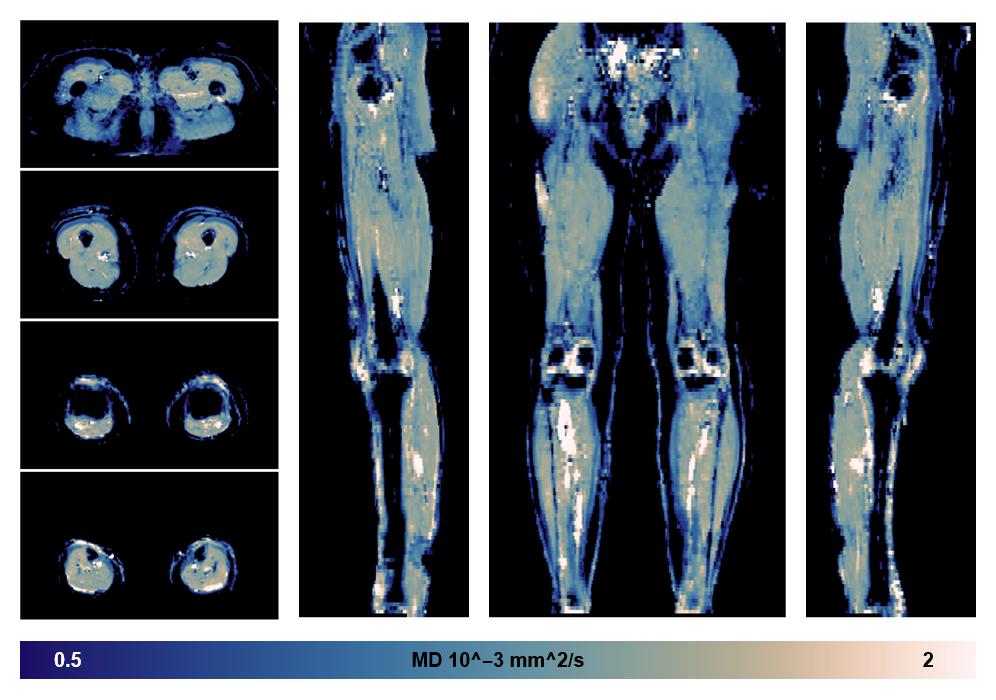

• Mean diffusivity

IVIM corrected whole leg muscle mean diffusivity obtained from diffusion tensor imaging.